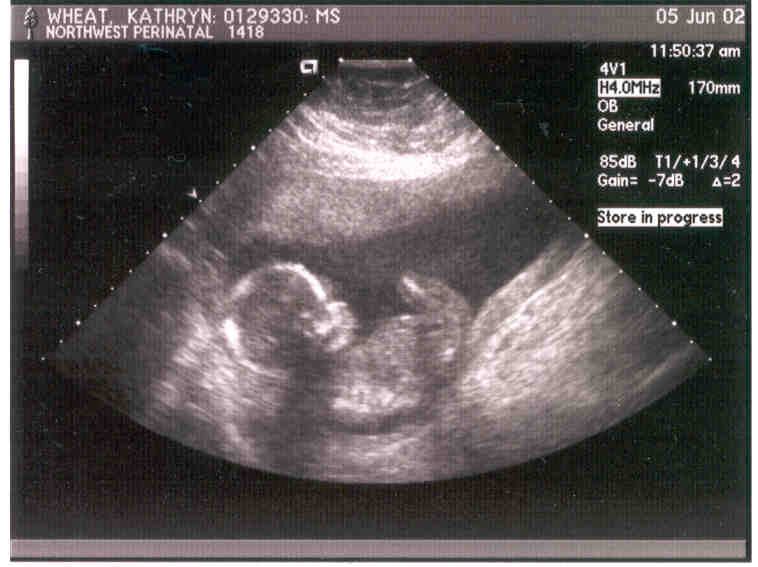

Our expected baby girl, Abigail Renee.

This is the 6-week ultrasound. What a cutie!

18 weeks. Can you tell the difference?

Look! She's waving.